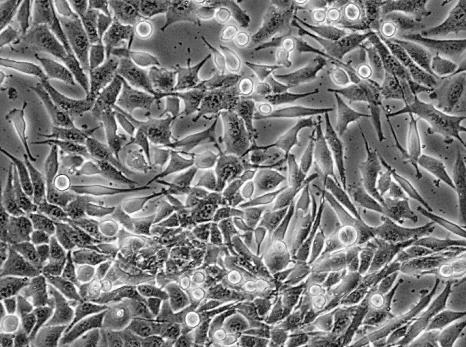

panc-1細(xì)胞 可分泌多種胰腺消化酶,包括胰蛋白酶、胰脂肪酶和胰澱粉酶等。這些酶的分泌對(duì)胰腺癌細(xì)胞的生長(zhǎng)和轉(zhuǎn)移起到重要的作用。panc-1細(xì)胞具有較高的增殖能力,在體外培養(yǎng)條件下可以快速增殖。

panc-1細(xì)胞是胰腺癌細(xì)胞的一種常用細(xì)胞系,用于研究胰腺癌、藥物篩選以及其他相關(guān)研究。為了保持細(xì)胞的生長(zhǎng)和狀態(tài)穩(wěn)定,定期進(jìn)行細(xì)胞傳代培養(yǎng)是必要的。本文將為您介紹panc-1細(xì)胞傳代培養(yǎng)的實(shí)驗(yàn)步驟,以幫助您高效地進(jìn)行實(shí)驗(yàn)。

panc-1是一種源自胰腺癌導(dǎo)管細(xì)胞的細(xì)胞系,其倍增時(shí)間為52小時(shí)。是目前應(yīng)用廣泛的胰腺癌細(xì)胞系之一,用于研究胰腺癌的病理機(jī)制、藥物篩選以及其他相關(guān)研究。由于市場(chǎng)上存在許多不同供應(yīng)商的panc-1細(xì)胞,選購(gòu)時(shí)需要注意一些重要的事項(xiàng),以確保獲取到高質(zhì)量的細(xì)胞,本文將為您提供一些選購(gòu)指導(dǎo)。